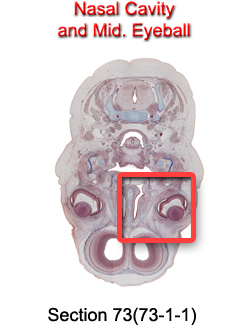

Nasal Cavity and Mid. Eyeball

Carnegie Embryo #9226

73-01-01